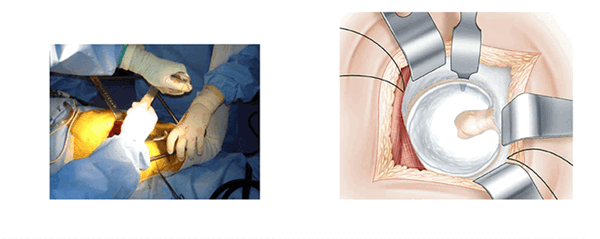

Задний доступ при малоинвазивном протезировании тазобедренного сустава

Заднебоковой доступ в настоящее время все шире применяется при малоинвазивном эндопротезировании тазобедренного сустава. Исторически так сложилось, что риск первичного вывиха при заднебоковом доступе случается чаще, чем при применении переднего или бокового доступа. Техника выполнения малоинвазивного метода с применением заднего доступа направлена на минимальное повреждение мышц и суставной сумки.

Сохранение мышц неповрежденными, или, по крайней мере, малоповрежденными, снижает риск вывиха протеза и ускоряет процесс реабилитации и восстановления двигательной функции конечности. Приводимое описание хода операции направлено на выявление трудностей, связанных с малым разрезом и сохранением мышц и связок. Особое внимание уделено четырем позициям, которые позволяют поочередно напрягать и расслаблять мягкие ткани и минимизировать вмешательство.

Техника операции

Начало операции, разрез поверхности. (L’abord superficiel)

Голеностопный сустав помещается на опоре. Колено согнуто и повернуто вовнутрь. Поверхность кожи обрабатывают антисептиком и делают разрез. В разрезе видна большая ягодичная мышца. Таким образом открывают операционное поле. Большая ягодичная мышца рассекается атравматическим способом снизу вверх по направлению волокон. В нижней части разреза рассечение широкой фасции облегчает манипуляции. В рану вводится рамка Шарнли. Она будет держать края большой ягодичной мышцы в течении всей операции. Передний клапан рамки располагается по направлению большого вертела.